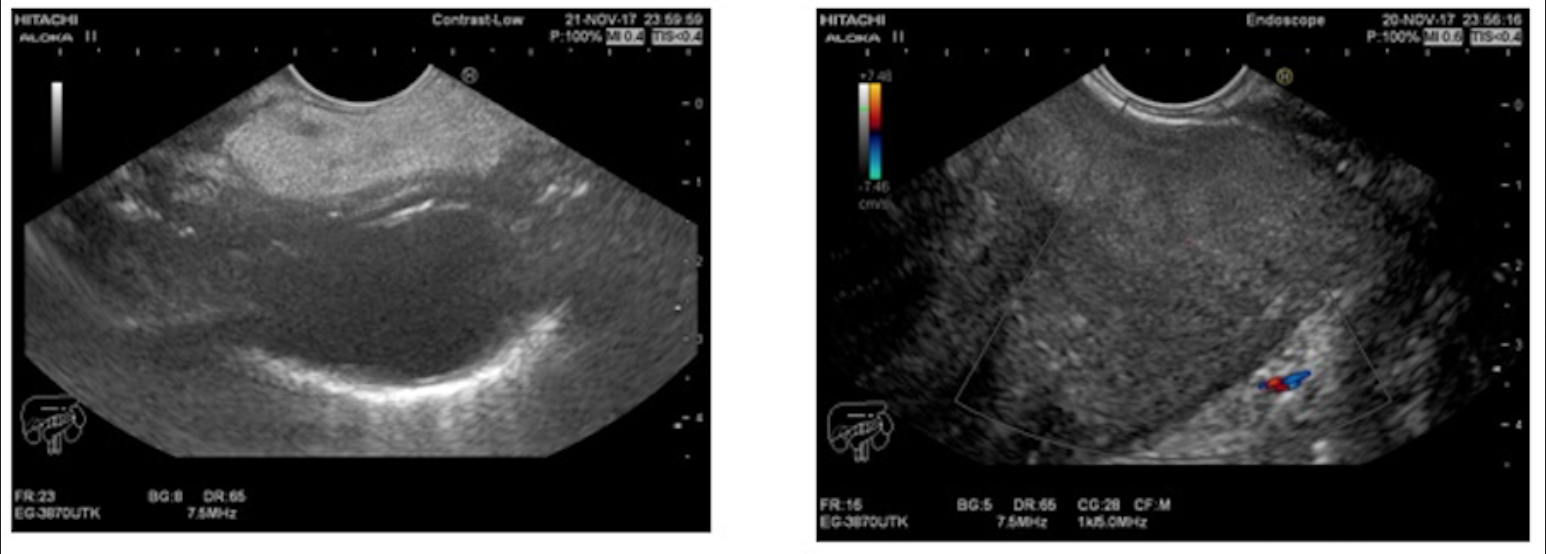

A 46 year old man presented to the gastrointestinal clinic complaining of dysphagia, regurgitation and a sensation of a lump in the throat, symptoms which have progressively worsened over the previous year. Upper GI endoscopy revealed a giant mass within the esophageal lumen, with a smooth surface covering, originated from the cervical esophagus, with a positive "squeeze sign". EUS imaging revealed a giant mobile lesion occupying the esophageal lumen.

What is the diagnosis?